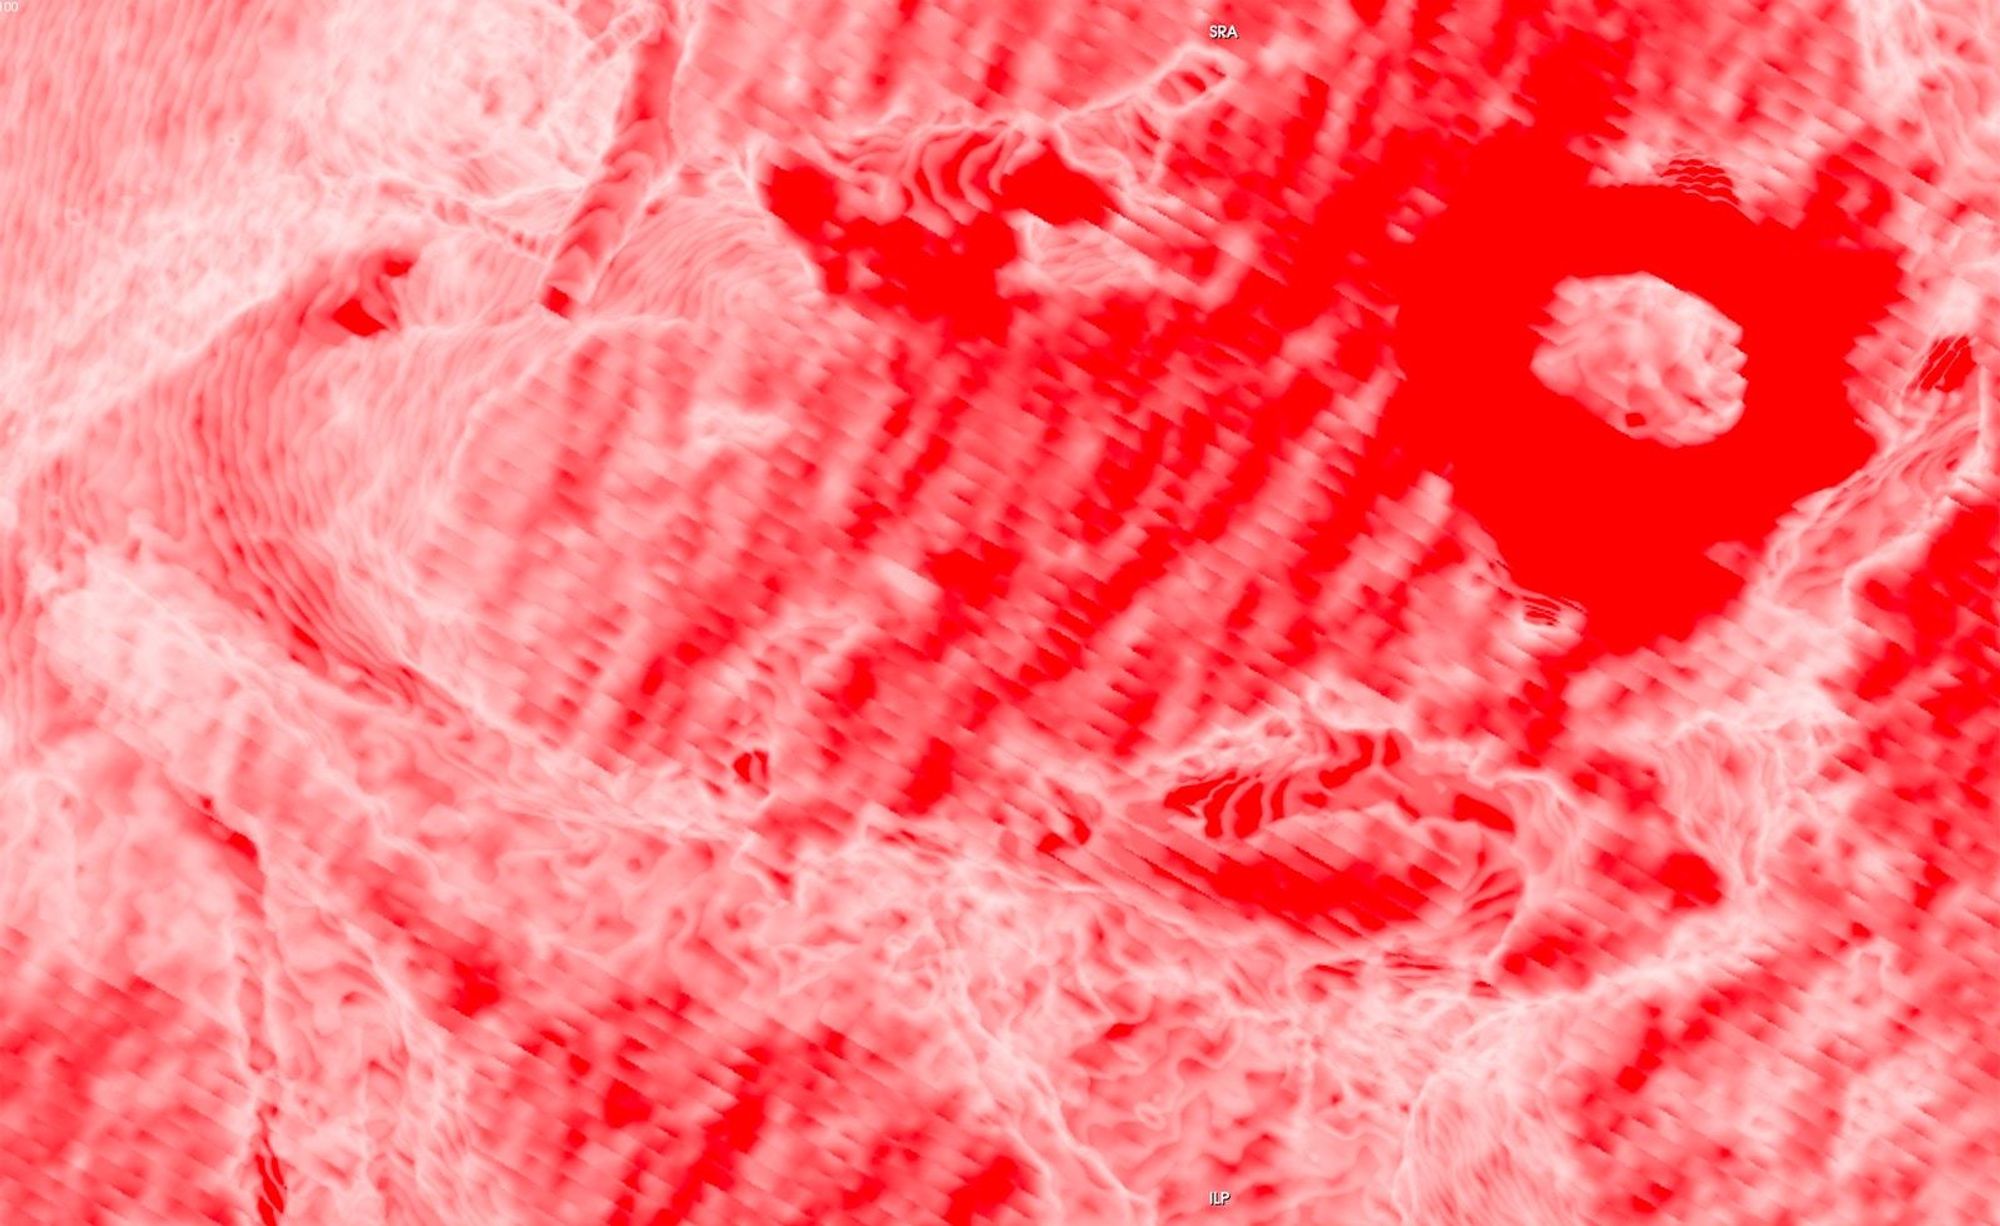

In this project, I look at the visual limit between the inside and the outside, the inner and the outer. I combine different visual approaches to materialise the body, using medical imagery, photography from manuals and radiology software. Decontextualised from their origin, these images speak of medicine’s relationship to both sex and violence, and remind us that, in medicine, to go into the body is always to go into the image first.